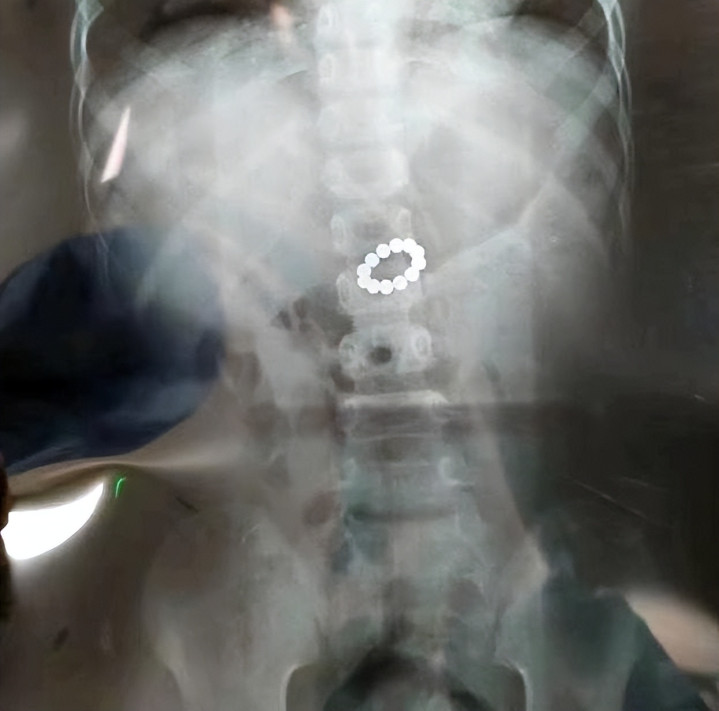

因为孩子吞了几颗这些磁力珠,就会在孩子的肠道互相吸引,夹在肠壁组织导致缺血穿孔,甚至会危及生命。

{jz:field.toptypename/}浙江一个5岁的孩子吞食了12颗磁力珠,最终要开腹手术才能脱离危险。